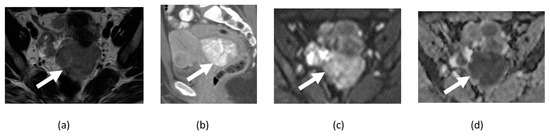

3.6. Ovarian Fibroma, Fibrothecoma, and Thecoma

4. Clinical Applications in Gynecological Malignancies

4.1. Cervical Cancer